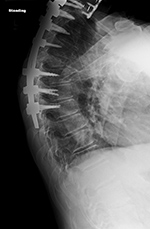

| Harms vertebral cage (AP view) |

Harms vertebral cage (lateral view) |